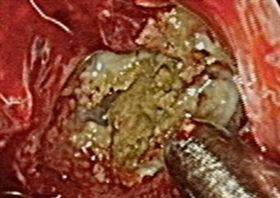

快臭死!熟男整天聞魚腥味「這疾病」上身

老是聞到揮之不去的「魚腥味」,可能與黴菌性鼻竇炎有關...